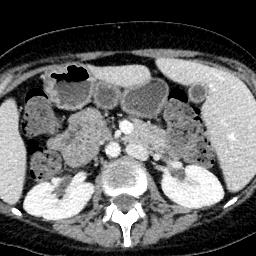

Due to the constraints of the imaging device and high cost in operation time, computer tomography (CT) scans are usually acquired with low intra-slice resolution. Improving the intra-slice resolution is beneficial to the disease diagnosis for both human experts and computer-aided systems. To this end, this paper builds a novel medical slice synthesis to increase the between-slice resolution. Considering that the ground-truth intermediate medical slices are always absent in clinical practice, we introduce the incremental cross-view mutual distillation strategy to accomplish this task in the self-supervised learning manner. Specifically, we model this problem from three different views: slice-wise interpolation from axial view and pixel-wise interpolation from coronal and sagittal views. Under this circumstance, the models learned from different views can distill valuable knowledge to guide the learning processes of each other. We can repeat this process to make the models synthesize intermediate slice data with increasing inter-slice resolution. To demonstrate the effectiveness of the proposed approach, we conduct comprehensive experiments on a large-scale CT dataset. Quantitative and qualitative comparison results show that our method outperforms state-of-the-art algorithms by clear margins.